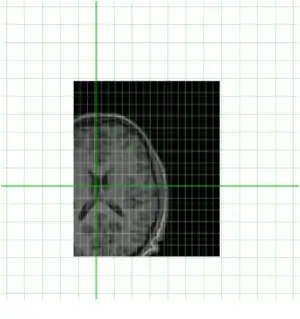

To get an idea of how they currently overlay I have put them together below

Clearly they are not aligned or "registered" to each other so we have to use a tool such as minctracc or mritoself in order to align them as such: